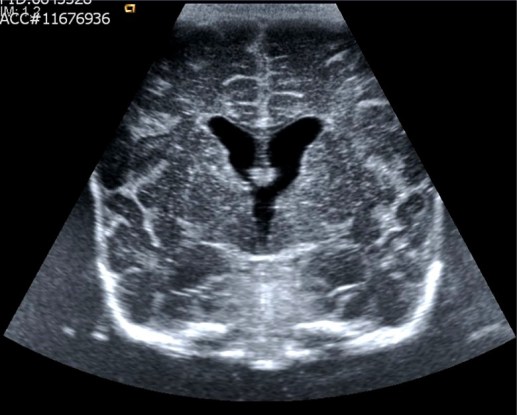

Anecoico: Negro, que no devuelve ecos. En la imagen que ves a continuación ves el corte coronal de un neonato en el contexto de una ecografía transfontanelar, se ven las circonvoluciones del cerebro y en el centro en forma de «Y» y completamente negro el líquido cefalorraquídeo en los ventrículos laterales.El LCR normal se ve así, negro, anecoico.

When we say that a structure is Hipo, Iso, Hiper – Ecoico, Ecogenic or Refringente – we do it because we compare it, usually, with the structure that we have next … I do not know if this has been very clear to you, but I explain it to you otherwise, with images … you’ll see how you understand it. Anechoic: Black, which does not echo. In the image that you see below you see the coronal cut of a neonate in the context of a transfontanel ultrasound, you can see the circonvolutions of the brain and in the center in the form of «Y» and completely black the cerebrospinal fluid in the lateral ventricles. Normal CSF looks like this, black, anechoic.

Imagen del LCR con aspecto Aneocico (Negro)